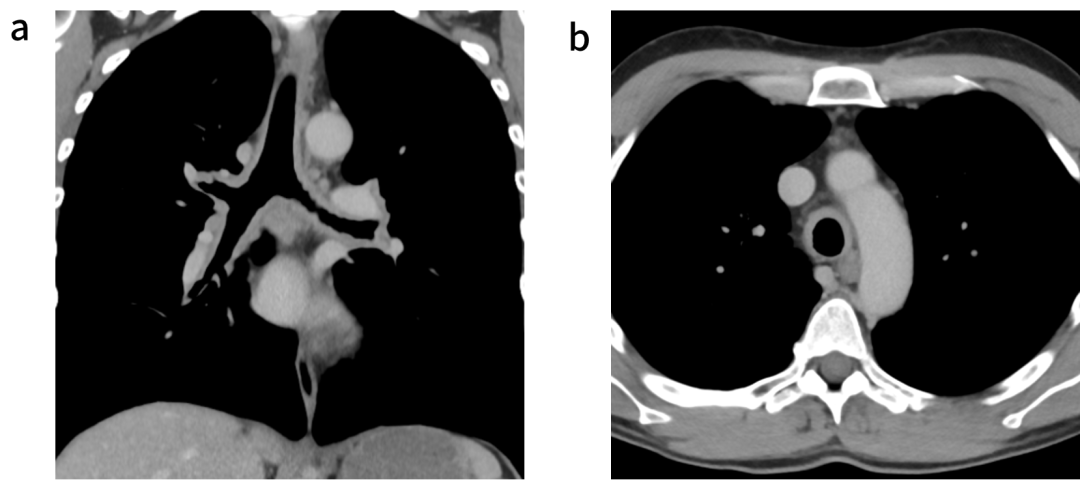

本例患者因临床疑诊RP转诊至风湿免疫科。虽曾考虑行组织活检以明确诊断,但因顾虑气道操作风险而未施行。治疗方案始于大剂量泼尼松龙诱导缓解,后续序贯生物制剂治疗。通过随访核磁共振成像(MRI)评估治疗反应,可见气管支气管壁增厚程度较前部分好转(图3、图4),提示治疗应答。尽管如此,患者仍反复出现呼吸道症状急性加重,说明本病具有易复发、难控制的临床特点。

3.治疗前颈部的轴向T1加权MRI(T1 FLEX+钆)显示气管壁增厚,对比增强,与炎症相符。